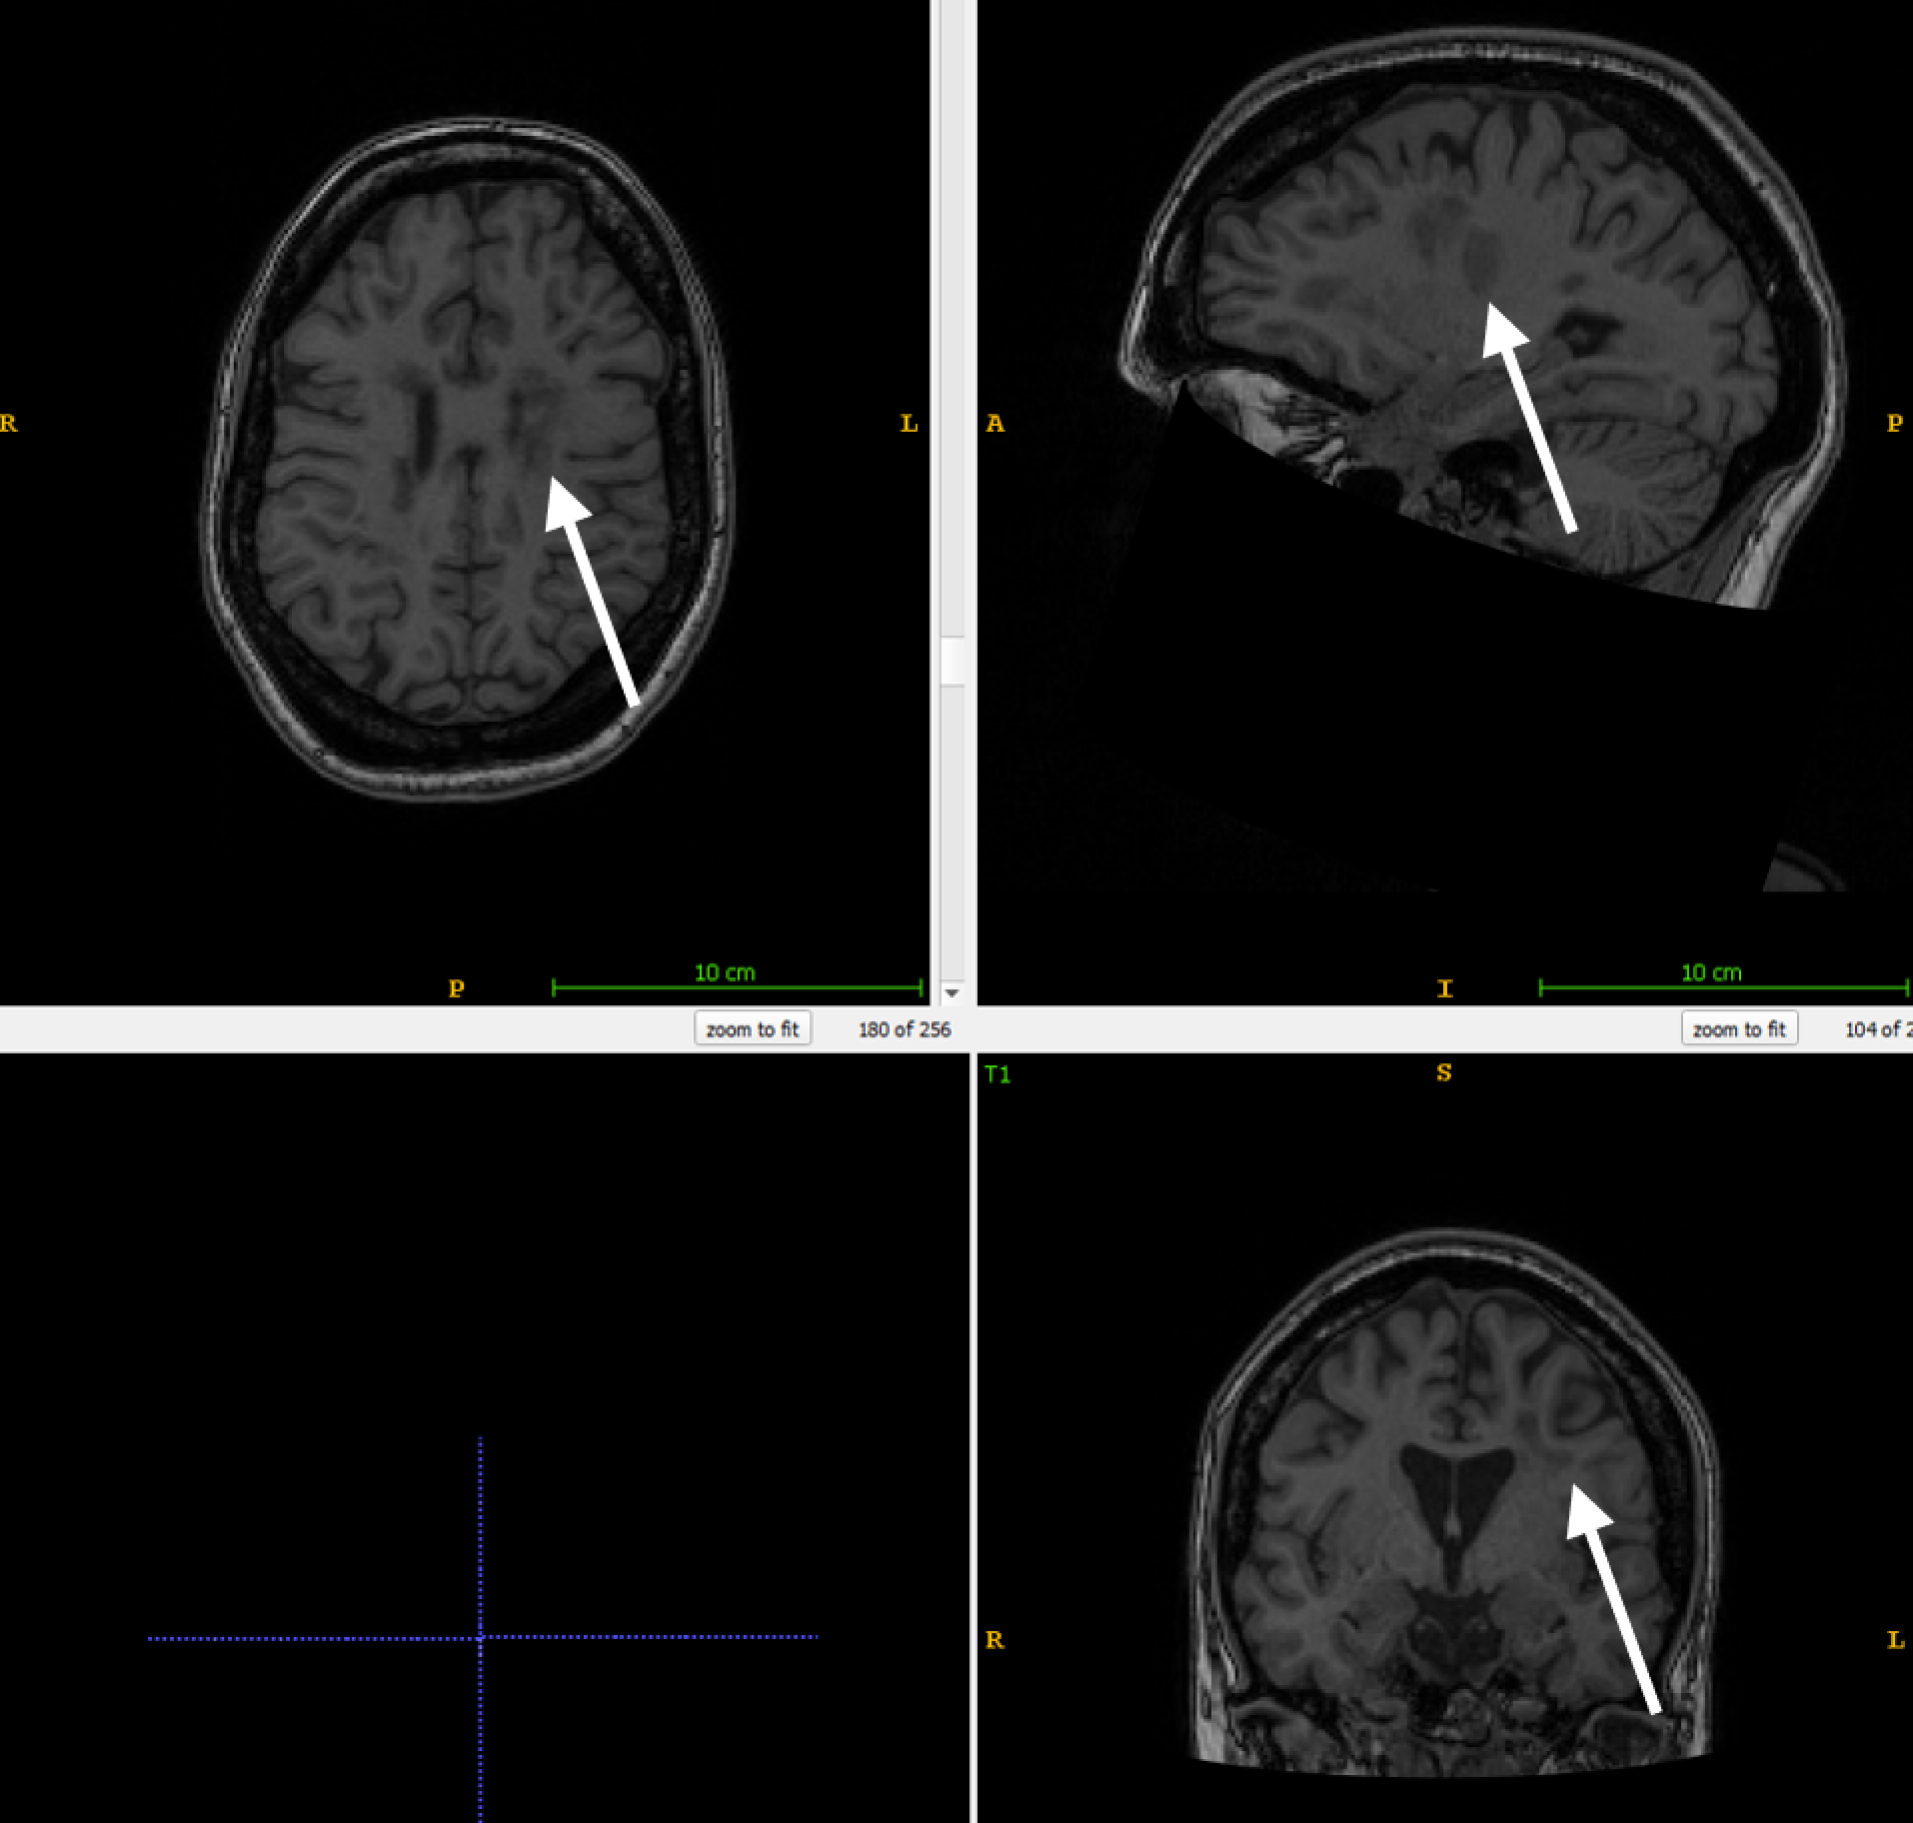

The impact of lesion filling on cortical thickness measurements was conducted using a test set composed of 65 patients diagnosed with RR-MS. This data originated from an internal longitudinal study conducted at the Insel hospital. All patients had been undergoing Natalizumab treatment for over two years and had at least four MRI scans performed over a period of approximately six months each, with corresponding clinical evaluations. MRI scans included a combination of 1.5T and 3T datasets with a slice thickness of 1mm or less in the T1w sequences. For each patient, the T1w and FLAIR images from their final visit, typically containing the highest lesion burden, were used for testing.

All T1w images undergo resampling to a standardized size of 256x256x256 voxels with a 1.0x1.0x1.0 mm voxel size and are reoriented to RAS orientation. FLAIR images are resampled to 160x256x256 voxels. The resampling process is carried out using nibabel.processing.conform [25]. Values below 0.01 are discarded as noise and the remaining data is scaled to the range [-1, 1]. A deep learning-based tissue segmentation is performed on the T1w images for each patient using the DL+DiReCT model [26]. To accelerate this process, the parallelization program GNU Parallel [27] is employed. For datasets with existing lesion masks, these are registered from FLAIR to T1w images using NiftyReg [28]. In the absence of lesion masks in the test set, a separate segmentation model DeepSCAN [29] is utilized to identify MS lesions. Only 2D slices containing WM, based on the DL+DiReCT segmentation, were incorporated for training.

Where N is the number of patients, the measurement before lesion filling, the measurement after lesion filling and the within-patient mean. This calculation is performed both for the global mean thickness (averaging the mean thickness of the left and right hemispheres) and across anatomical regions defined by the Desikan-Killiany (DK) atlas [42]. Since ANTs and ANTsPyNet do not deliver regional statistics, for those methods we average over the parcellation derived from DL+DiReCT. In a subanalysis, we excluded cases with MS lesions located near the cortical surface (juxtacortical lesions) which might lead to lesion-filling errors: to identify patients with juxtacortical lesions, the binary lesion masks are dilated by one pixel and multiplied with the tissue segmentations. Patients with lesions outside WM are excluded in the second analysis.